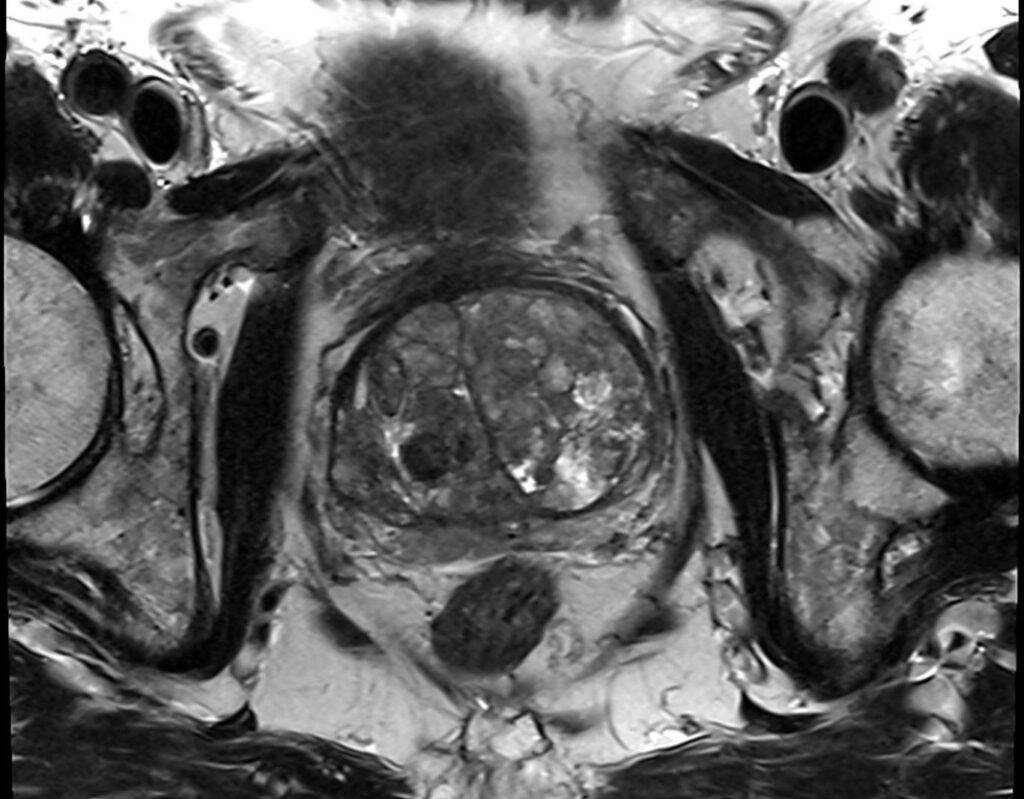

Über Magnetfelder wird ohne Strahlenbelastung das Körperinnere mit einem exzellenten Weichteilkontrast in hoher Auflösung dargestellt und ermöglicht eine präzise Beurteilung der Gewebeveränderungen.

Die MRT der Prostata erfolgt „multiparametrisch“ mit standardisierten Protokollen.

Mittels eines Bewertungssystems (PI-RADS-Score) werden die MRT-Bilder der Prostata ausgewertet und klassifiziert, als eine standardisierte Interpretation zur detaillierten Einschätzung des Prostatakrebsrisikos.

Die Prostata wird mit hochaufgelösten MRT-Bildern in allen Ebenen und mehreren Ansichten dargestellt sowie mittels verschiedener Funktionsmessungen analysiert.

Zunächst liegt der Fokus darin, in der Struktur und Signalgebung verändertes Drüsengewebe von gesundem Gewebe abzugrenzen. Als nächstes gilt es, verändertes Gewebe mit Funktionsmessungen (wie z.B. Zelldichte und Durchblutung) zu charakterisieren. Die diffusionsgewichtete MRT-Sequenz macht sichtbar, ob in verändertem Gewebe eine erhöhte Zelldichte – wie bei einem Prostatakarzinom – vorliegt. Die dynamische kontrastmittelangehobene MRT-Sequenz lässt Prostatakrebsareale mit einer erhöhten Durchblutung abgrenzen.

Als eine nicht-invasive Methode ist die MRT der Prostata eine schonende und völlig schmerzfreie Untersuchung, die frühzeitig eine Unterscheidung zwischen bösartigen, entzündlichen oder leichten Prostataveränderungen ermöglicht. Unabhängig der Prostatagröße ist die gesamte Prostata präzise beurteilbar und gewährleistet sogleich ein „Staging“ möglicher Prostatakrebsherde bezüglich Lage, Größe, Charakteristika und Ausbreitungsgrad.

Die multiparametrische MRT ist hierbei bildgebend die genaueste Methode im Nachweis von therapiebedürftigem Prostatakrebs, dass bei frühzeitiger Diagnose gute Heilungschancen hat. Sie liefert entscheidende Hinweise zur sodann ggf. gezielten Punktion der Prostata und Behandlung der Erkrankung.